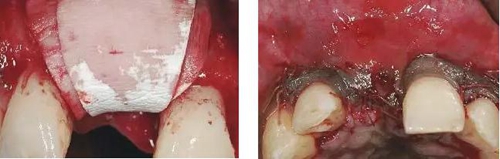

圖8、從上腭獲取結(jié)締組織縫合在黏骨膜瓣上,進(jìn)行軟組織增量。為了使得黏骨膜瓣充分減張情況下關(guān)閉,應(yīng)該使用瓣的分層技術(shù)。使用6-0或者5-0的可吸收線縫合關(guān)閉傷口。4個(gè)月后進(jìn)行二期手術(shù)時(shí)通過(guò)分裂瓣技術(shù)將色素沉著的牙齦向冠方復(fù)位以恢復(fù)其原來(lái)的自然外形(在此沒(méi)有展示)。

圖9、種植體植入5個(gè)月:種植體到唇側(cè)骨板的距離仍然大于2mm,這對(duì)于形成長(zhǎng)期穩(wěn)的美學(xué)效果有很重要的作用。